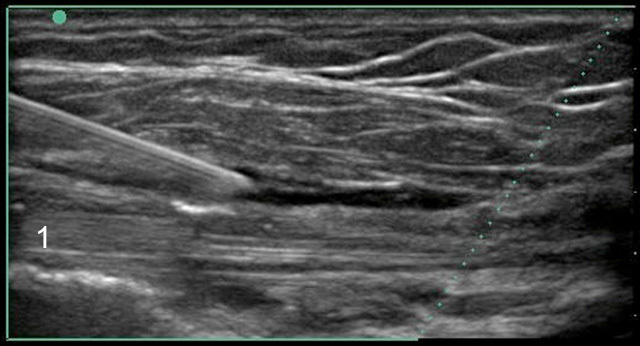

Image - Épaule : Tendon du biceps, Injection dans la gaine, Coupe grand axe

Tendon du biceps